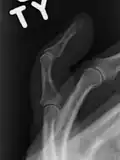

Un dedo en martillo sin una fractura asociada